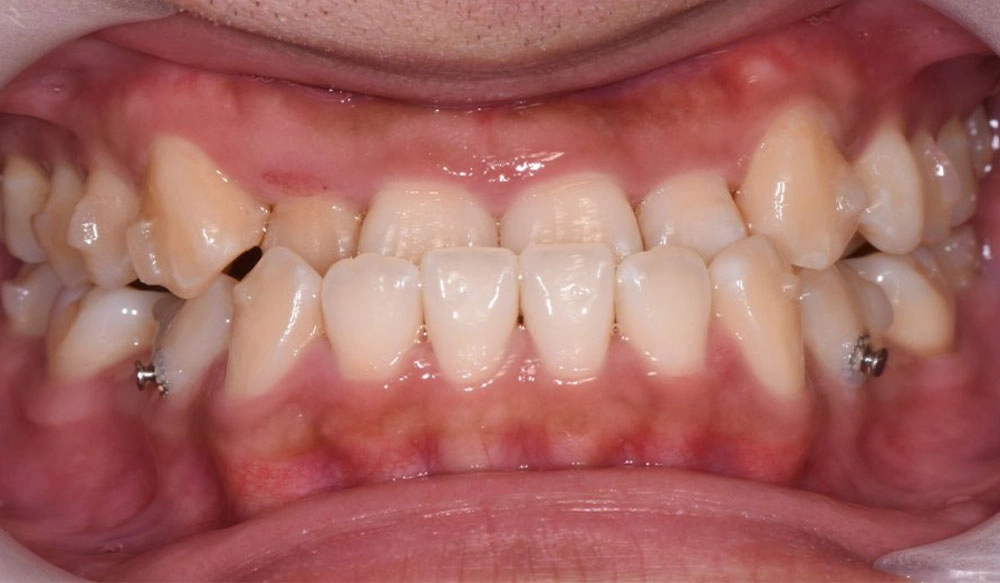

Chen chúc

Chen chúc là tình trạng có sự chênh lệch giữa kích thước răng và không gian có sẵn để sắp xếp răng trên cung răng.

Thông tin bệnh nhân:

Tuổi: 17

Giới tính: nữ

Lựa chọn điều trị Invisalign: Invisalign Comprehensive

Tổng thời gian điều trị:

29 tháng